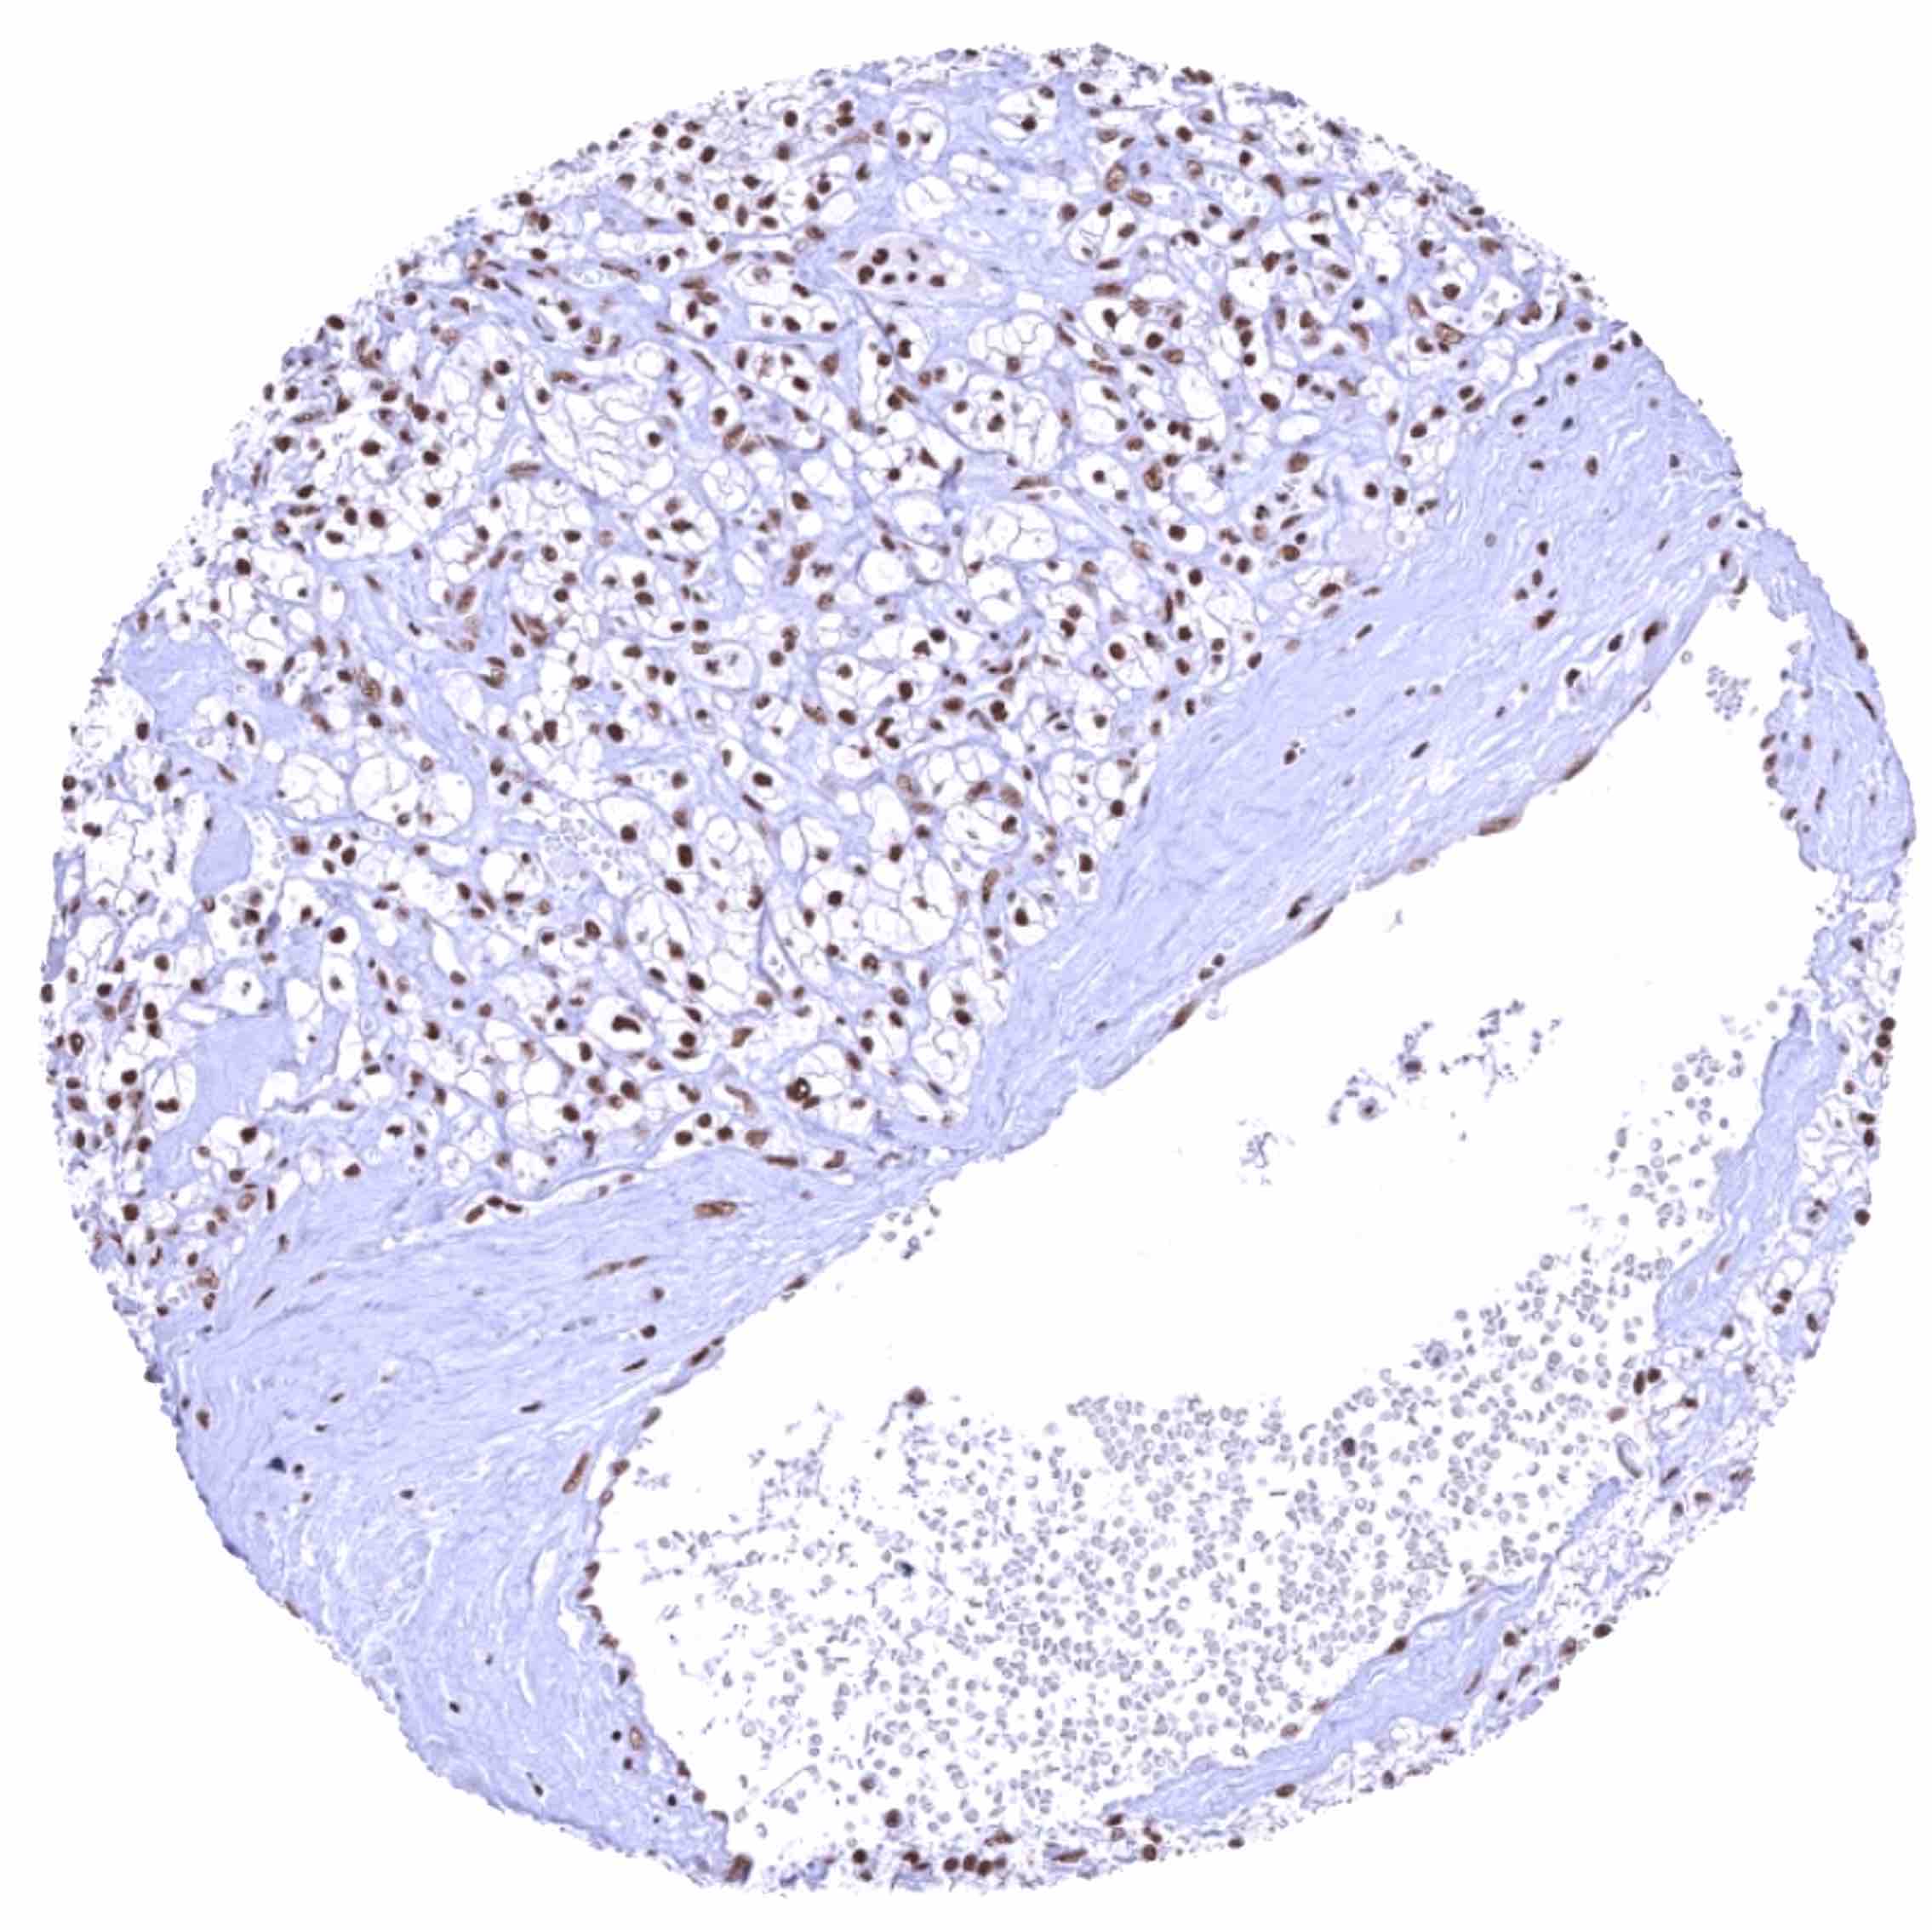

Kidney – Clear cell renal cell carcinoma with strong BRD4 staining of all tumor cells.